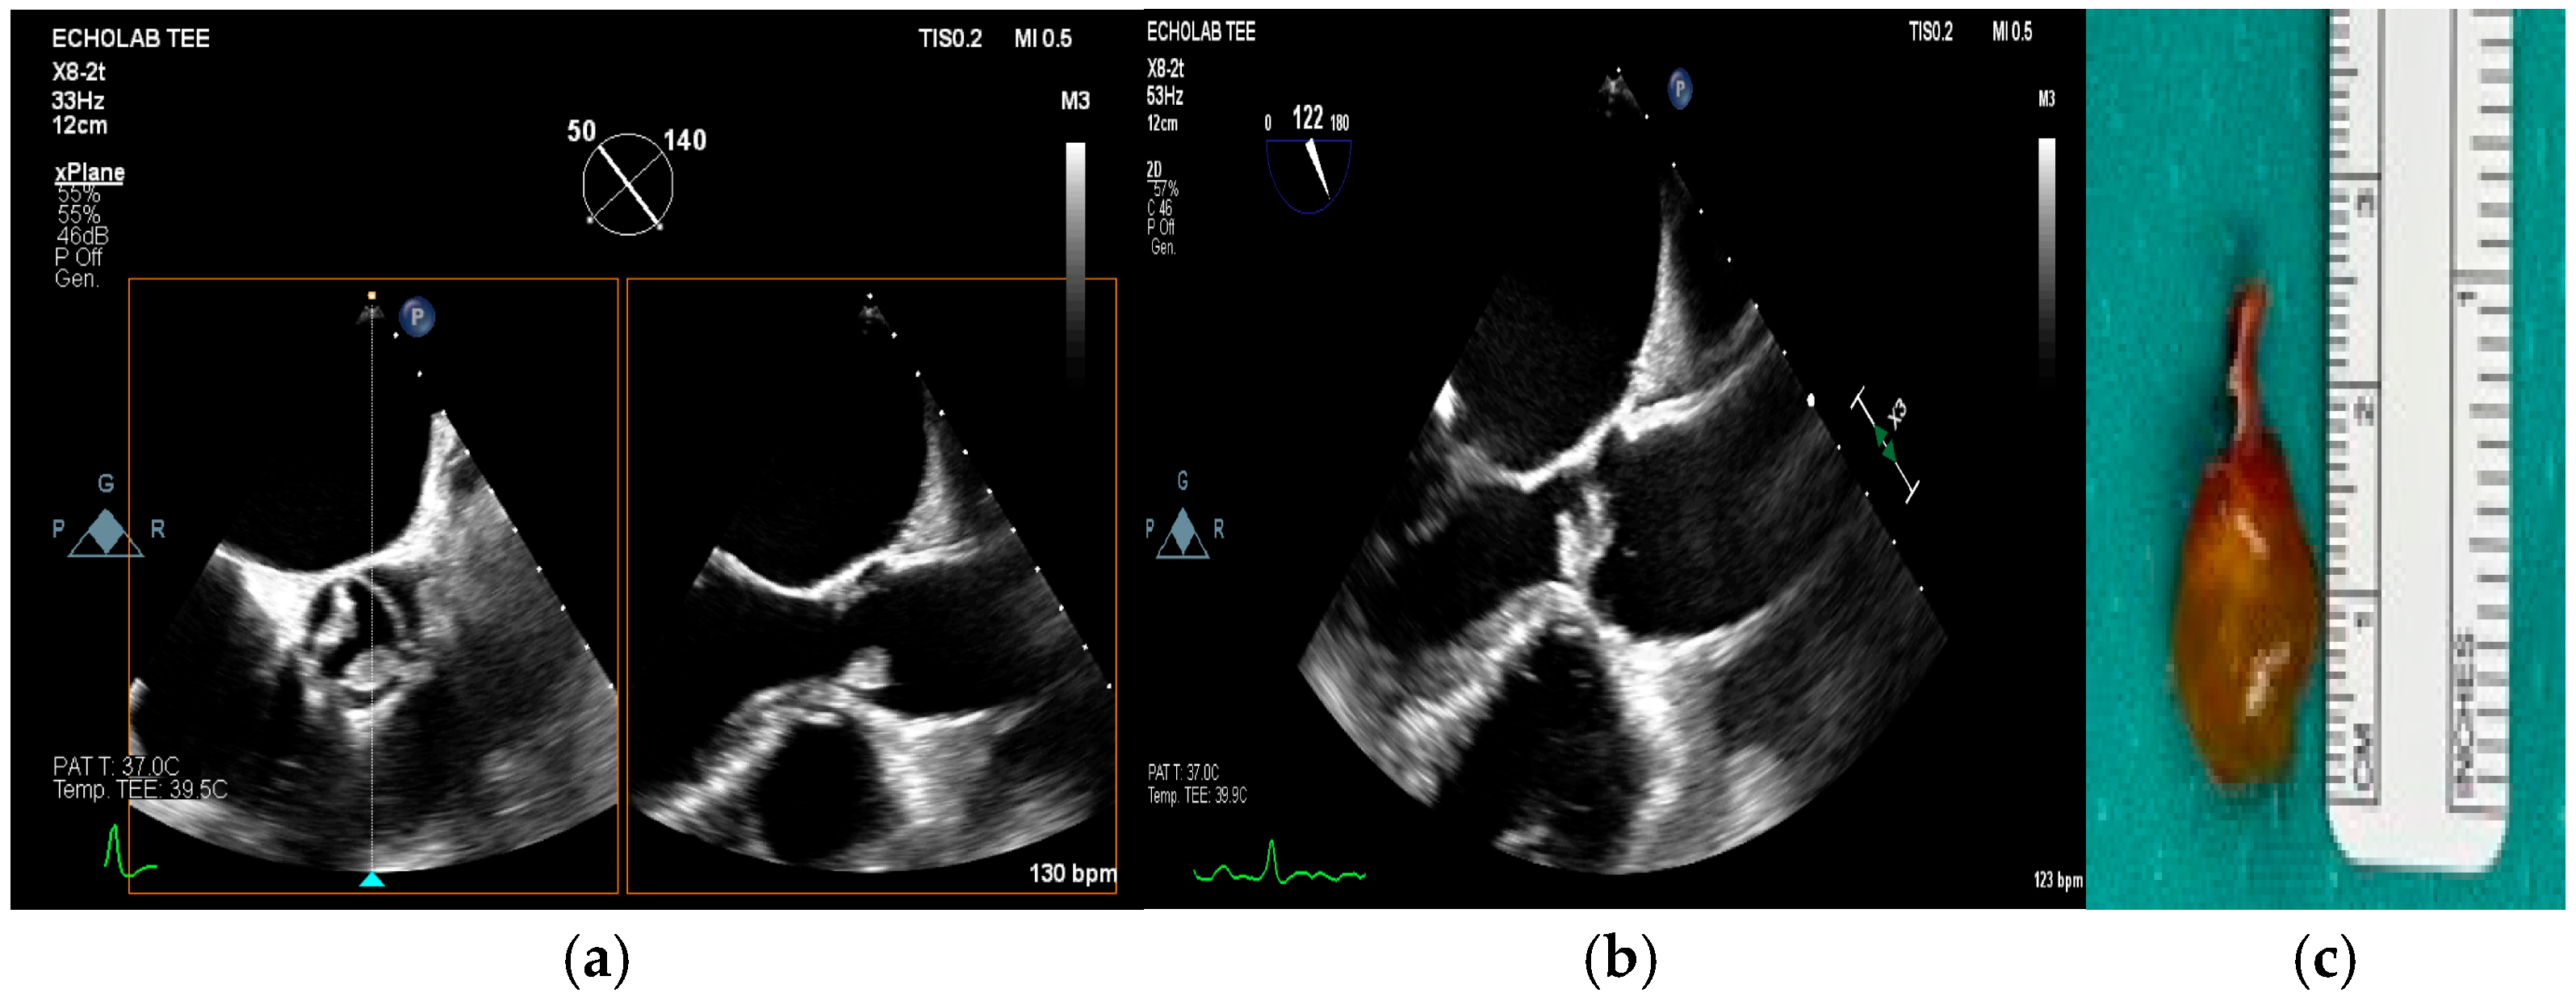

4. Echocardiography

- valvular or leaflet perforation, i.e., tissue defects causing valvular regurgitation originating from the site of perforation.

- valvular aneurysm, a saccular outpouching of a valve leaflet, protruding into the atrium or ventricle.

- perivalvular or perigraft abscess, an echolucent or echodense area adjacent to the valve annulus or prosthetic ring often with irregular borders and sometimes with evidence of cavity formation.

- pseudoaneurysm, a contrast-filled outpouching with a narrow neck communicating with the cardiac lumen, often adjacent to the valve annulus. On echocardiography, it appears as a pulsatile cavity with systolic expansion and diastolic collapse.

- intracardiac fistula, visualized as an abnormal communication between cardiac chambers or vessels, is often detected by using color Doppler.

- significant new valvular regurgitation compared with previous imaging, i.e., increase in regurgitant jet size, vena contracta width…